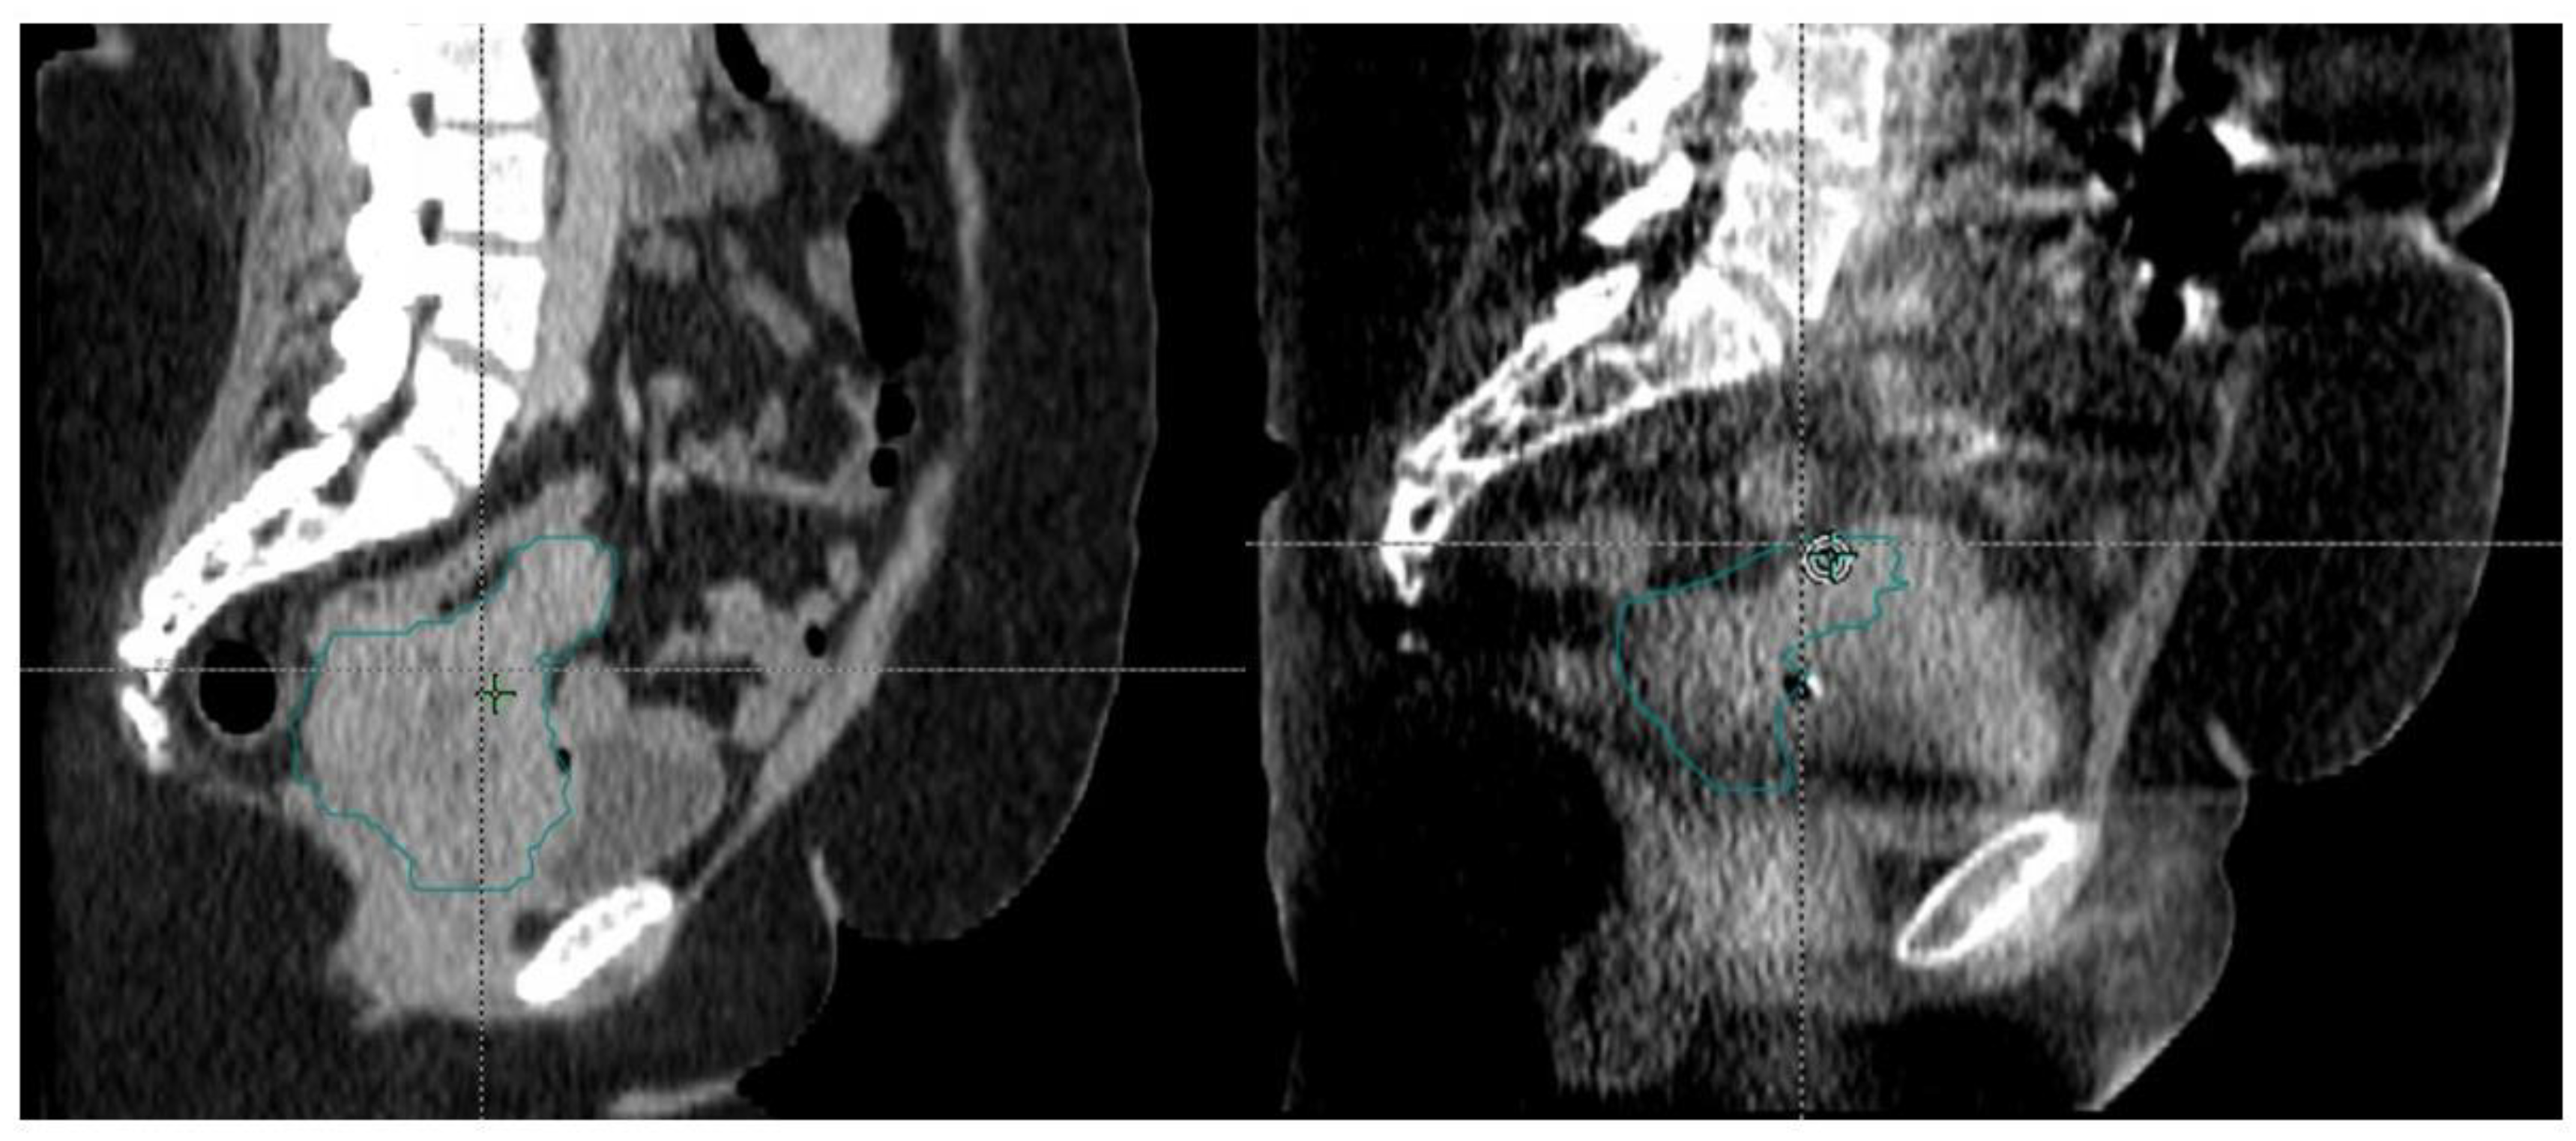

In the modern era of IMRT, patients with gynecological cancer who are planned for radiotherapy undergo a process called CT simulation. This step involves patients undergoing a CT scan, which radiation oncologists use to delineate targets and nearby normal structures in a process called contouring. Additional imaging with MRI and PET/CT can also help to better delineate structures. Targets including the cervix, uterus, vagina, and pelvic lymph nodes are contoured and constitute the gross tumor volumes (GTV) and clinical tumor volumes (CTV), which represent gross disease and microscopic disease, respectively. The CTV is further expanded to create a planning tumor volume (PTV). This expansion is conducted to account for errors during the delivery of radiation as well as potential movement of organs not only during treatment delivery, but throughout the course of fractionated treatments of radiotherapy. Nearby organs are also contoured including the rectum, bladder, sigmoid, bowels, femurs, and kidneys. An example of a GTV, CTV, and PTV is shown in Figure 2.

Figure 2. Representation of GTV, CTV, and PTV. A gross lymph node represents the GTV in red. The pelvic lymph node basin is the CTV in yellow with a 5 mm expansion to create the PTV in orange.